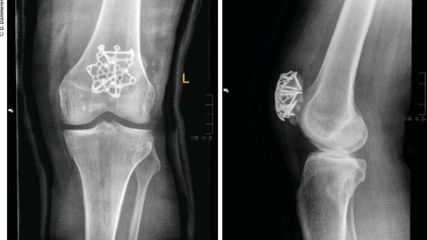

Die Patellafraktur ist eine seltene (1%), aber komplikationsbehaftete Fraktur.1 Bei fast einem Drittel der Patienten kommt es postoperativ zu belastungsabhängigen Schmerzen, chronischen ...